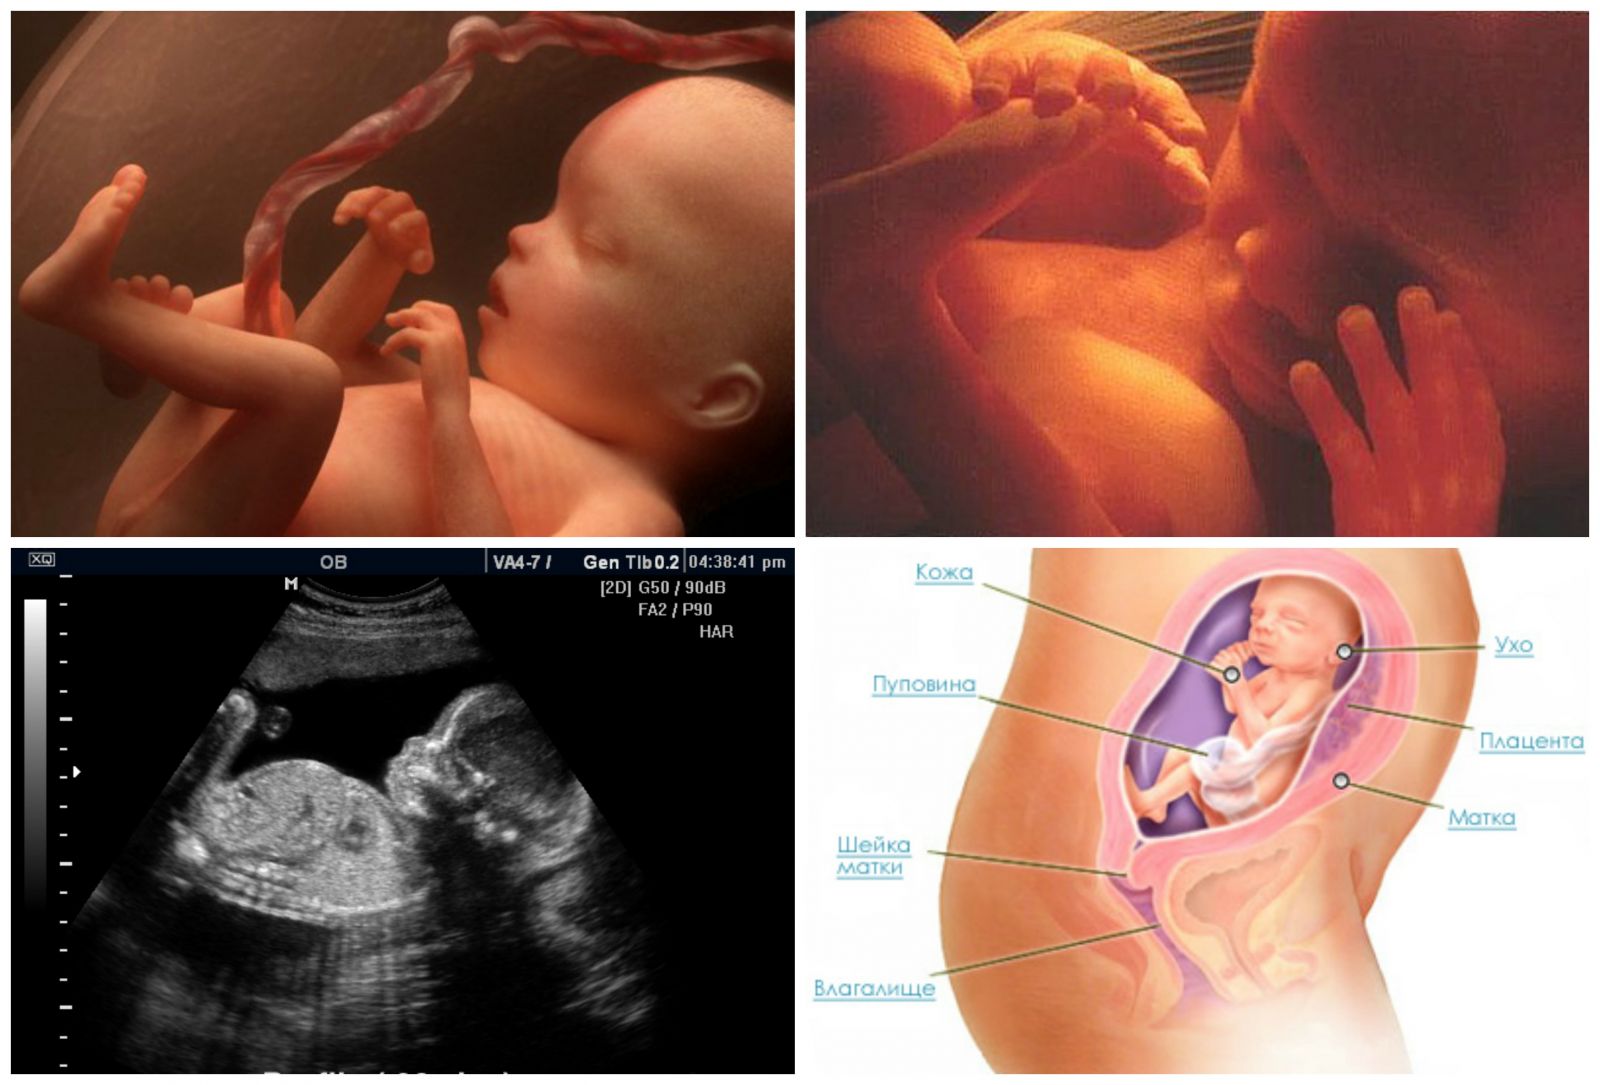

- Быстро развивается головной мозг. Именно в это время малыш начинает изучать себя и то, где он находится с помощью тактильных ощущений. Именно на 22 неделе беременности ребенок пробует шевелить пальчиками, касаться стенок плаценты и себя. Такое исследование ребенком пространства своего обитания будет усиливаться именно на 22 неделе, так что беременная мама будет хорошо ощущать его прикосновения.

- Во время планового УЗИ на 22 неделе беременности на тельце малыша появляются еле заметные волосики, похожие на пух. Они формируют некий вакуум вокруг плода, задерживающий первородную смазку. Кроме этого, смазка защищает ребенка от соприкосновения с водной средой околоплодных вод. Непосредственно перед родами, волосики за ненадобностью исчезают, а предродовая смазка обеспечивает легкий выход малыша из утробы матери.

На 22 неделе беременности плод продолжает развиваться и весит уже около 450 граммов. Его длина составляет примерно 27 см. Наблюдается активное формирование мозга и нервной системы, а также развитие мышц и костей. Появляются пальчики на ногах и руках, формируются пальцы. Органы слуха продолжают развиваться, а кожа покрывается слоем мягкого волосяного покрова.

Вес ребенка составляет около 680-700 граммов, а рост порядка 22 см. Малыш активно обрастает жирком, идет развитие его костной и мышечной ткани, совершенствуются внутренние органы.

Все части лица уже хорошо сформированы. На глазках есть веки, которые приоткрываются. Выросли реснички и бровки, которые иногда хмурятся. Мимика ребенка пока не сознательна. Если сделать УЗИ в 22 недели, будет видно не только, что происходит с плодом, но и все его структуры лица. Причем, если малыш займет удобное для врача положение, уже можно будет понять, на кого из родителей он больше похож, чей у малыша рот или нос. На память можно будет сделать фото и видеозапись.

У некоторых малышей на голове растет уже много волосиков. Другие почти лысенькие. Но волосы, даже если они есть, пока не имеют цвета, пигмента в них нет. У всех малышей на этом сроке беременности волосы белоснежные.

Пока малыш находится в животике у мамы, он получает кислород через плаценту. Но к моменту рождения его легкие должны быть готовы к самостоятельному дыханию. Поэтому, уже с этого срока начинает вырабатываться вещество под названием сурфактант, которое позволяет держать легкие расправленными, не допускает их склеивание.